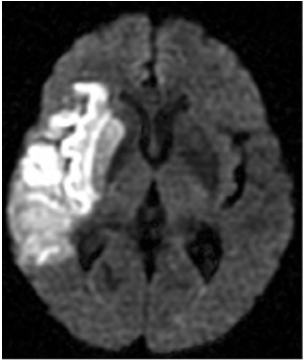

56.附圖是一張DWI的影像,右大腦一片相當亮的區域代表:

(A)急性腦內出血 (B)急性腦梗塞(infarction) (C)亞急性腦內出血 (D)慢性腦梗塞